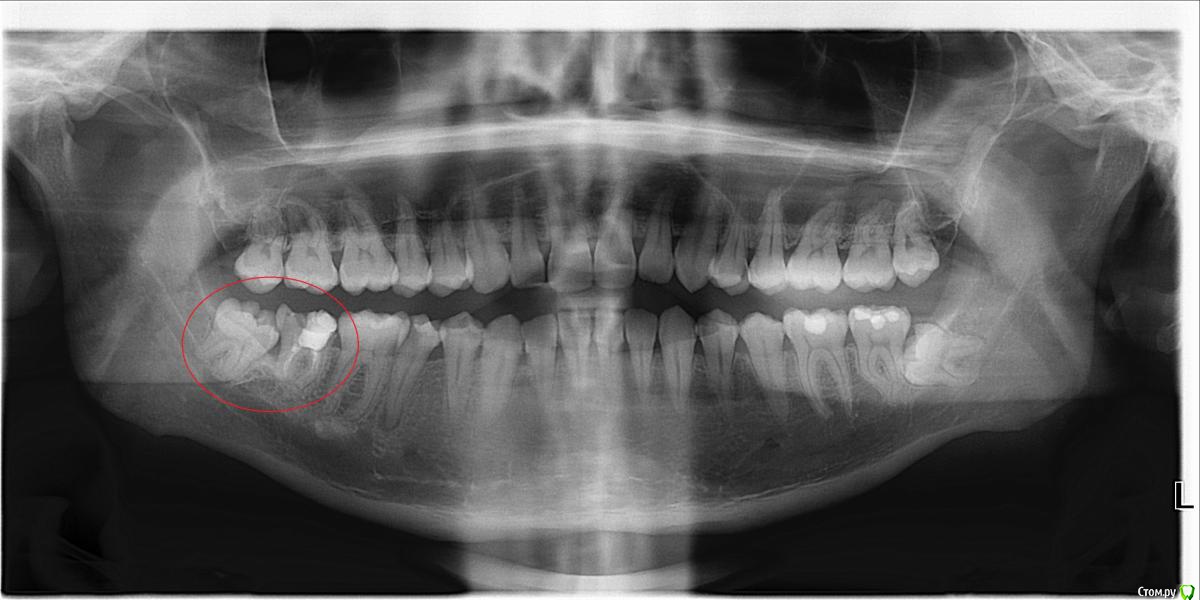

Boris87 Опубликовано 21 марта, 2020 Поделиться Опубликовано 21 марта, 2020 (изменено) Здравствуйте. В 2008 г. нижняя семёрка была депульпирована. Не беспокоит, но откололся небольшой край зуба (года 2 назад уже), и вокруг пломбы уже кариес. Иногда когда ем из того места чувствуется неприятный привкус. Рядом на восьмёрке небольшой кариес, и она упирается в край 7-го. Походил по клиникам. Одни говорят - восьмёрку удалять, на семёрку коронку. Другие - что и семёрку удалять. Ещё в одной сказали что восьмёрку даже можно оставить, пролечив кариес, и обточив семёрку чтобы ей не мешала + коронку, но другие говорили что так никто не обтачивает. В одной клинике говорили что могут просто нарастить светоотвержд. материалом. Я конечно хотел бы этого. Коронку не хочется (читал что металл в организме у многих потом проблемы вызывает, даже рак, особенно если никель в составе). А полностью диоксид циркония дорого, и не уверен что оправданно (зуб потом наверное всё равно удалять). Как тут лучше поступить? ЗЫ. ОПТГ делал в октябре, после этого 5-й зуб был пролечен, а КТ - недавно. Изменено 21 марта, 2020 пользователем Boris87 Ссылка на комментарий

red_butler Опубликовано 21 марта, 2020 Поделиться Опубликовано 21 марта, 2020 Восьмой удалять, седьмой убрать пломбу и кариес и принимать решение, но на фото прогноз седьмого зуба плохой 1 Ссылка на комментарий

DmitrySH Опубликовано 21 марта, 2020 Поделиться Опубликовано 21 марта, 2020 Восьмой удалять, седьмой убрать пломбу и кариес и принимать решение, но на фото прогноз седьмого зуба плохойСогласен. По фото мало понятно. Ссылка на комментарий